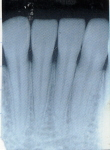

歯周病は歯の周囲組織を破壊していく病気です。その進行過程では歯の周囲骨の吸収も起こるため、レントゲン写真により骨の状態も検査します。

| 正常な歯 | 歯周病に罹患した歯 |